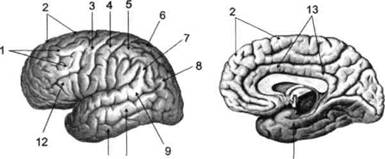

Поверхность полушарий покрыта бороздами и извилинами, причем величина и форма борозд подвержены значительным индивидуальным колебаниям, вследствие чего не только мозг различных людей, ной полушария одного и того же индивида по рисунку борозд могут заметно отличаться друг от друга (рис. 15). Глубокими постоянными бороздами пользуются для разделения каждого полушария на большие участки, называемые долями. Такими бороздами являются боковая (сильвиева) борозда, центральная (роландова) борозда и те-менно-затылочная борозда, отчетливо обозначенная лишь на поверхности продольной шели мозга, делящей его на два полушария (рис. 16). Основные извилины показаны на рис. 17.

Рис. 16. Основные борозды больших полушарий головного мозга:

/ — продольная щель; 2— роландова (центральная) борозда; 3— сильвиева (боковая)

борозда; 4— поясная борозда; 5— теменно-затылочная борозда; 6— шпорная борозда;

7— коллатеральная борозда; 8— гиппокампальная борозда

Рис. 17. Основные извилины больших полушарий головного мозга:

Рис. 18. Островок

/ — средняя лобная; 2 — верхняя лобная; 3 — передняя центральная; 4— задняя центральная;

5 — нижняя теменная долька; 6 — верхняя теменная долька; 7— надкраевая; 8 — угловая; 9 —

верхняя височная; 10 — средняя височная; // — нижняя височная; 12 — нижняя лобная; 13 —

поясная; 14— морского коня (гиппокампальная или парагиппокампапьная)